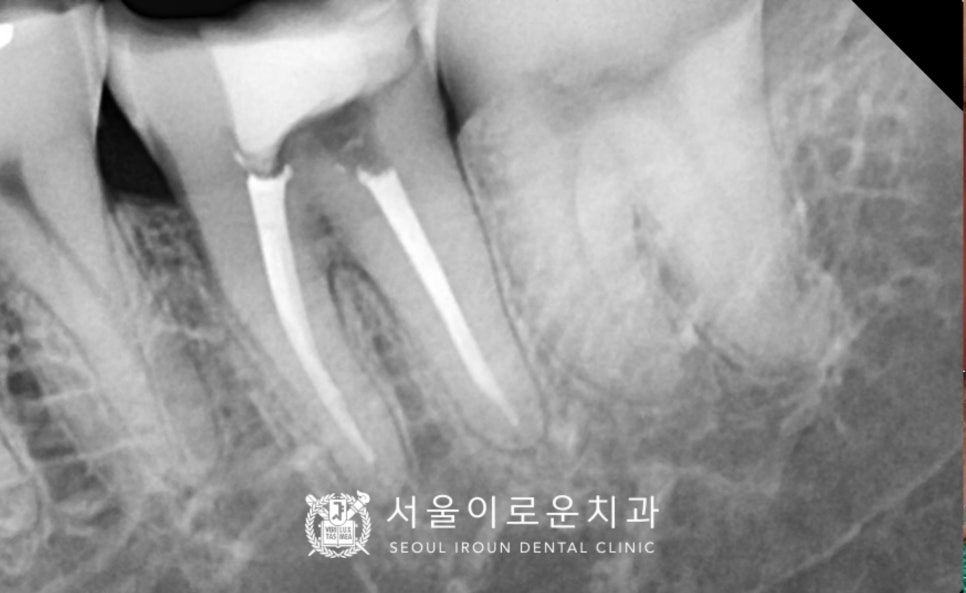

x-ray 상 치아 안쪽 신경조직까지

충치가 진행되어 있는 상태로

신경치료 후 크라운 수복이 필요하였는데요.

아래턱 왼쪽 두 번째 큰 어금니(#37)의

충치를 남김없이 깨끗하게 제거한 후

감염된 신경을 제거하는

신경치료를 꼼꼼하게 마무리하였으며,

충치로 인해 제거된 치아머리 일부를

단단한 레진으로 보강하여

형태를 다듬은 후

크라운 제작을 위한

인상채득을 진행하였습니다.

단단하면서도 치아와 유사한 색상을 가진

지르코니아 보철물로 마무리해 드렸습니다.